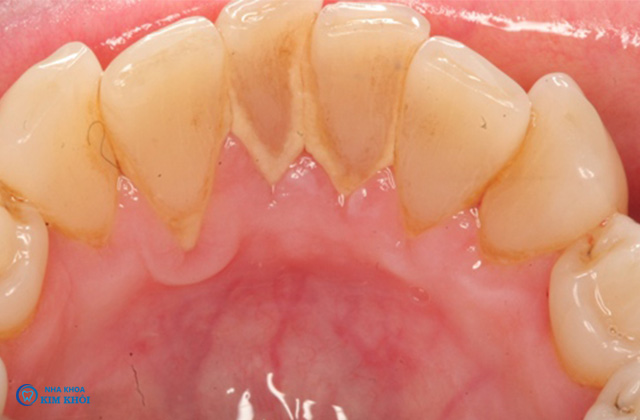

Vôi răng hay cao răng là những mảng bám mảnh vụn thực phẩm còn sót lại sau khi ăn. Đã bị vôi hóa bới vi khuẩn có trong nước bọt muối canxi carbonat và calcium phosphate. Mảng bám thức ăn thường lắng đọng thành lớp dày ở thân răng, nướu có màu trắng đục hoặc vàng nâu mất thẩm mỹ và gây tổn hại nhiều đến răng miệng.

2, Những tác hại của vôi răng đối với sức khỏe răng miệng

Hơi thở nặng mùi

Phá hủy men răng khi mảng bám tích tụ quá nhiều, dày và lâu ngày. Nguy cơ sâu răng càng cao nếu men răng bị tổn thương càng nặng.

Nơi cư ngụ của nhiều loại vi khuẩn lên men răng. Carbohydrate tạo ra acid gây sâu răng như Streptococcus mutans, Lactobacilli...

Tác nhân gây ra các bệnh ở miệng, họng: viêm niêm mạc miệng, viêm họng, viêm amidan, lở miệng...

Gây chảy máu chân răng, ê buốt khi ăn uống.

Hiện tượng tụt nướu làm lộ chân răng.

Đây là nguyên nhân chính gây ra các bệnh răng miệng. Những bệnh như viêm nha chu, tiêu xương ổ răng, viêm tủy răng ngược dòng. Có thể khiến răng lung lay, rụng răng gây mất thẩm mỹ.